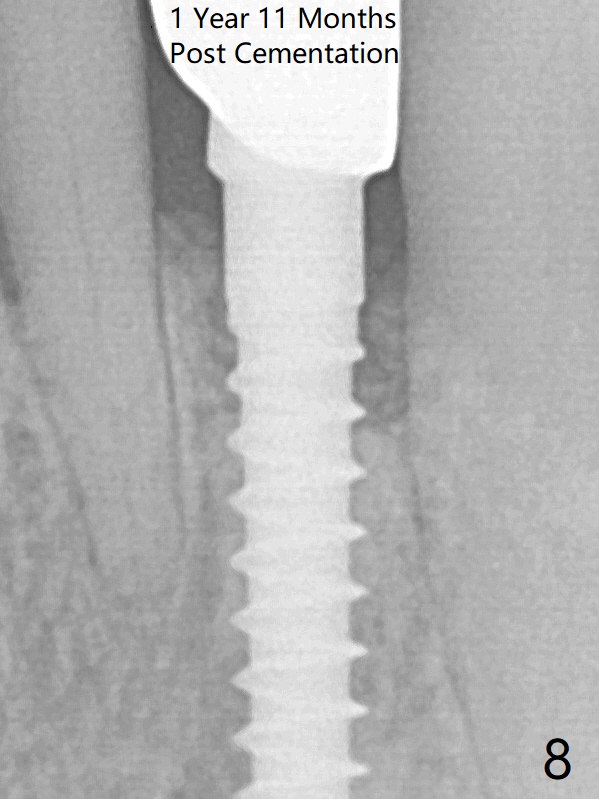

The gingival depth is measured 2-4 mm after extraction. The 1st intraop PA taken with 1.2 mm drill for 16 mm shows the mesiodistal width is 5.11 mm (Fig.2); a 2.5x14(2) mm 1-piece implant is placed with >35 Ncm (Fig.3 with allograft placed). There is no bone loss 3 months postop (Fig.5). The distal crest seems to be reduced in density and lower in height 1 year 7 months (Fig.7) and 1 year 11 months (Fig.8) post cementation. The severity does not worsen probably related to use of water pik.